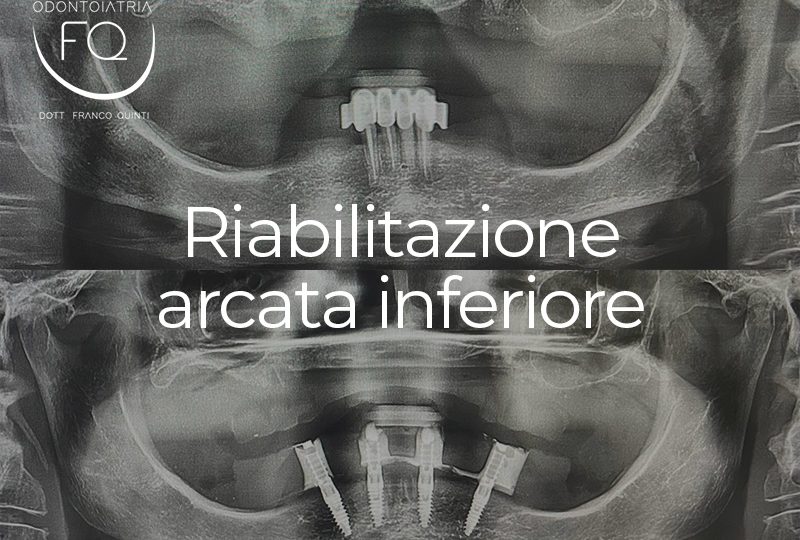

Oggi vi presento un caso di riabilitazione dell’arcata inferiore eseguito con l’utilizzo di dime scomponibili.

Il trattamento ha previsto l’inserimento di 4 impianti Prama Power di Sweden & Martina e la contestuale riabilitazione protesica provvisoria. Tra 3 mesi il caso verrà finalizzato con una protesi definitiva.